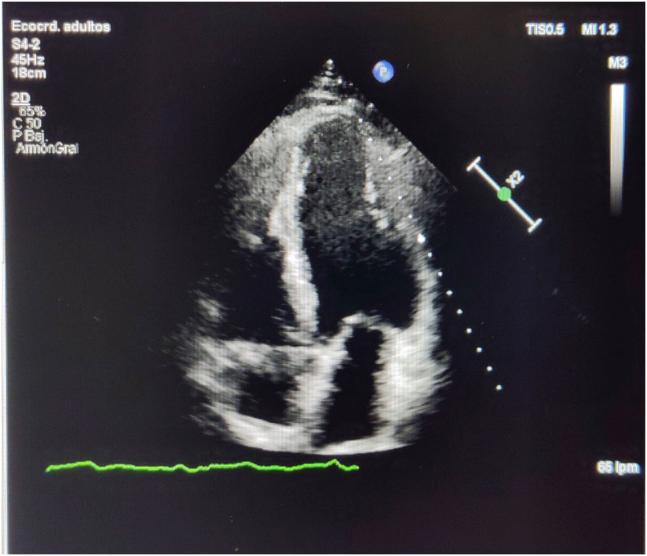

Critical role of cardiac magnetic resonance in the diagnosis of left-dominant arrhythmogenic cardiomyopathy: A paradigmatic case in a recreational middle-aged athlete.

HeartRhythm Case Rep. 2021 Apr 9;7(7):453-456. doi: 10.1016/j.hrcr.2021.03.026. eCollection 2021 Jul.